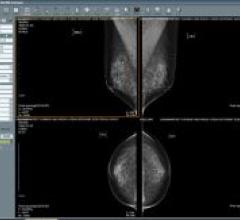

GE's Senographe Essential is the digital mammography platform for the future. It allows precision imaging women in a single exposure or view. The enlarged detector easily accommodates large breast images without degradation of small breast images. Digital capabilities optimize workflow and connectivity, while providing 3D images and capacity for interventional mammography procedures.